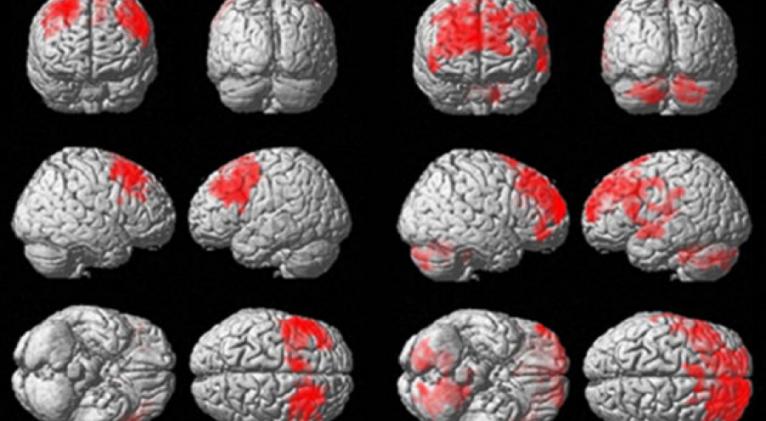

Pero, ¿cómo afecta la práctica de este deporte a la actividad cerebral de los jugadores aunque no aparezca la temida encefalopatía? Para comprobarlo, el equipo de Adam Hampshire ha realizado un estudio comparando la actividad cerebral de 13 exjugadores de la liga profesional NFL y 60 voluntarios sanos y les ha sometido a una serie de pruebas mientras registraba la actividad de su cerebro. El resultado, publicado en la revista Scientific Reports, apunta a que las personas que han jugado a este deporte presentan una serie de disfunciones ejecutivas y cambios en la conectividad como consecuencia de los impactos.

En la figura que ves sobre estas líneas, por ejemplo, puedes el resultado de una serie de resonancias magnéticas funcionales de ambos grupos. Las barras de la izquierda indican la conectividad en los jugadores y las de la derecha, la conectividad del grupo de control. Lo que han visto los científicos es que se produce una hiperactividad de determinados circuitos (más actividad para la misma tarea) y una conectividad menor en el lóbulo frontal, que se correlaciona además con el número de impactos que cada jugador sufrió durante su vida deportiva.

Llama la atención que estas diferencias se apreciaron cuando se realizó un examen con escáner, pero no en las pruebas ejecutivas. Lo que indican estos resultados es que los exjugadores deben reclutar más áreas del cerebro para realizar las mismas tareas cognitivas, y esto puede provocar un deterioro general del sistema a largo plazo. Aún así, se necesita repetir este tipo de pruebas a mayor escala, y con más ex jugadores voluntarios, un colectivo, apuntan los científicos, al que no es fácil convencer para participar en estos experimentos.